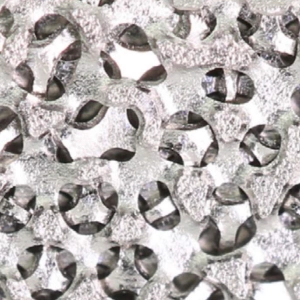

Deeply porous titanium scaffold with interconnected pores averaging 523 jim, and pore interconnections averaging 229 pm in diameter.

Titanium + PEEK-Optima interdigitation. Best of both materials.

Superior x-ray visualization of bridging bone and the implants orientation.